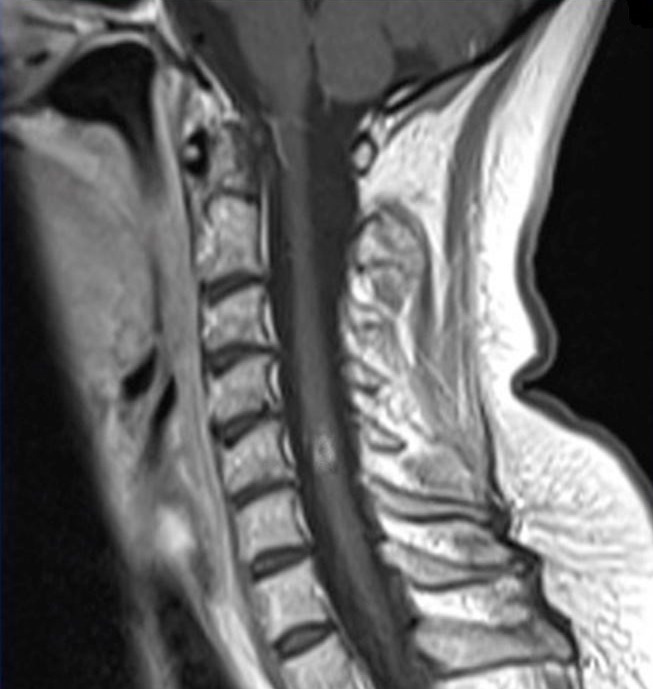

Vous réalisez donc une IRM médullaire centrée sur l’étage cervical dont est extrait le cliché suivant :

Il s’agit d’un cliché d’IRM médullaire en séquence T1 avec injection de gadolinium.

La séquence FLAIR est utilisée pour l’IRM cérébrale et non pas pour l’IRM médullaire.

Les séquences utilisées en pondération T2 pour les IRM médullaires sont : le T2 simple, le T2 STIR (inversion, récupération) et le T2 FATSAT (saturation de graisse).

T1 : LCR noir, lésion en hyposignal.

T1 avec injection de gadolinium : LCR noir + prise de contraste de la lésion (en hypersignal) si l’inflammation est active, ce qui signifie qu’il existe une rupture de la barrière hématoméningée.

T2 : LCR blanc, graisse blanche, lésion en hypersignal.

T2 STIR : LCR blanc, graisse grise, lésion en hypersignal.

T2 FAT SAT : LCR blanc, graisse grise, lésion en hypersignal.

Il n’existe pas de malformation d’Arnold-Chiari.